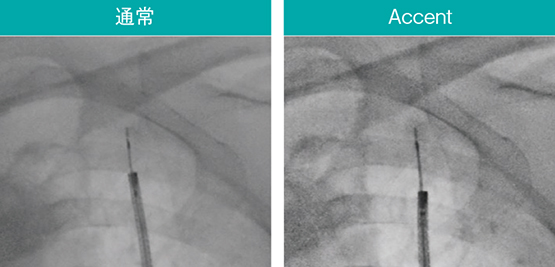

内視鏡検査に用いるデバイスは通過性や柔軟性が優先され、透視下での視認性に課題がある製品もある。Ultimax-i の新画像処理条件「Accent」は、ガイドシースや生検針などのデバイスや関心領域を強調し、より手技がしやすい環境を提供する。実際の透視像(図7〜9)でも、Accent適用により腫瘤やEBUSプローブ、ガイドシース、ブラシなどのデバイスが明瞭に確認できる。

図7 AccentによるEBUSプローブや関心領域の強調

スコープ:BF-MP290、EBUS:UM-S20-17S(オリンパス社製)